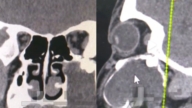

报导提到,13岁的高明(化名)在连续十多天出现多饮、多尿和不明原因消瘦后,突然高烧、呼吸急促。送至医院时,其肺部影像已显示大面积变白,也就是“白肺”,被确诊为甲流合并急性呼吸窘迫综合征、脓毒症休克,病情危急,需立即启用ECMO。经救治,该患儿已转危为安。